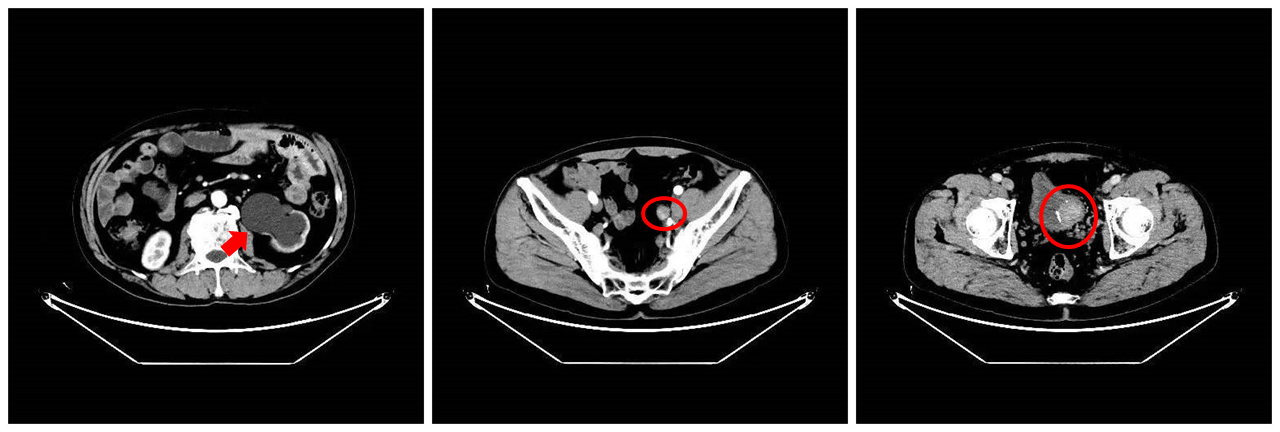

CT检查提示患者体内有肾积水(左图红色箭头处)与肿瘤(中图与右图红色圆圈处)

今年61岁的巴桑,最近半个多月来发现自己间断性地出现血尿,虽然不疼但还是赶紧前往当地医院进行超声检查,结果发现左侧输尿管末端出现病变。为寻求进一步治疗,患者来到拉萨市人民医院泌尿外科,靳松为其安排全腹增强CT等相关检查,在排除泌尿系结核病史后,靳松高度怀疑患者所患为尿路上皮癌,结合病理活检结果,最终确诊患者为左侧输尿管及膀胱肌层润性尿路上皮癌(高级别),同时已经转移扩散至淋巴结。

患者的输尿管下段边缘已产生钙化,肿瘤已深入膀胱,血供丰富,并与周围肿大淋巴结及膀胱周围脂肪粘连紧密,手术存在大出血风险;左侧输尿管及左肾有积水现象,左肾萎缩,腹腔环境复杂。为减少术中损伤与术后转移复发,促进术后恢复,靳松在认真研究病历资料后,决定为患者实施“腹腔镜下左肾切除+左侧输尿管全段切除+膀胱袖状切除”手术,并制定术后药物化疗与膀胱灌注疗法。